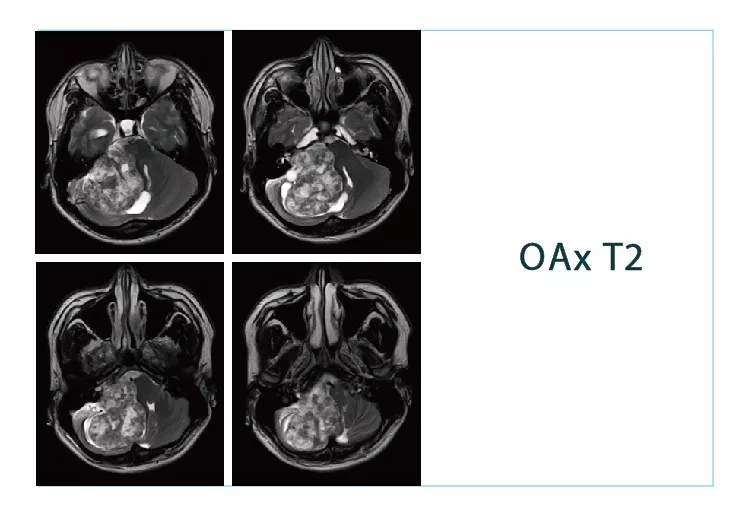

【朗润影像档案】磁共振影像病例分享(编号20180831)